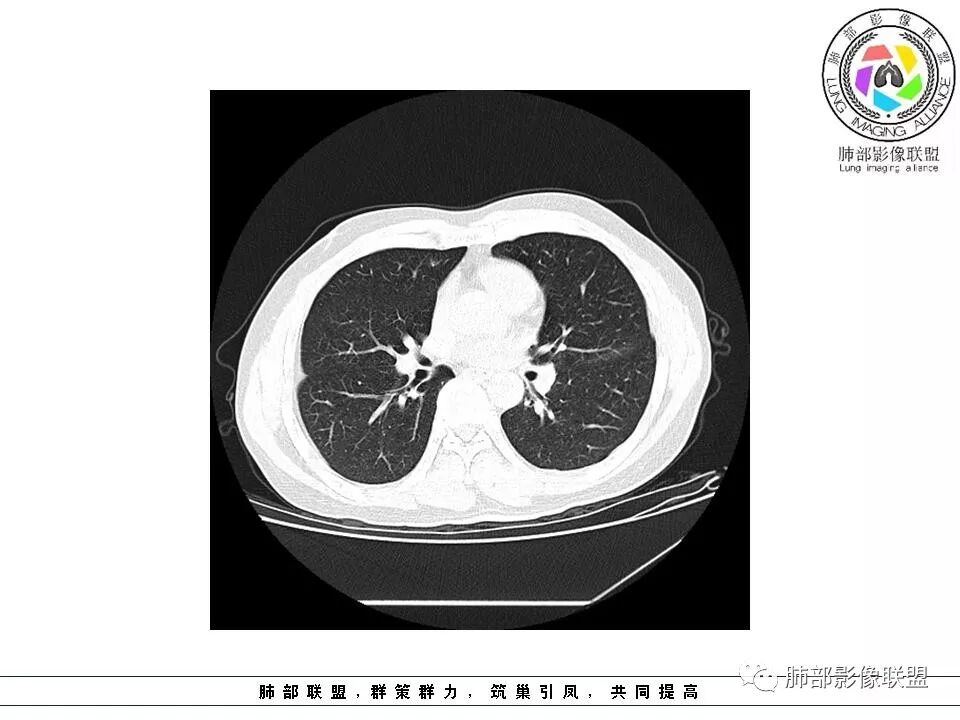

南边:51岁男性,体检发现右肺结节这个年龄段的男性,啥都可以发生,也属于肺癌的高危人群南边:首先是实性还是GGO?好像实性吧

密度遮盖了血管这是血管吧

这些?

这个?

如果实性病变,边缘收缩,可以考虑炎性, 但是边缘有边界清楚GGO,一定要警惕恶性,还有粗短毛刺更要小心撇开其它,看到这个图,除非你怀疑假象,不然就是要考虑腺癌的可能